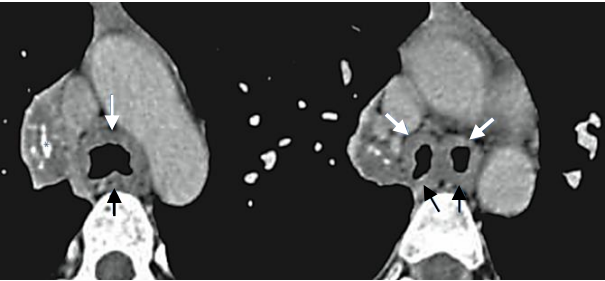

As imagens a seguir são sugestivas de: